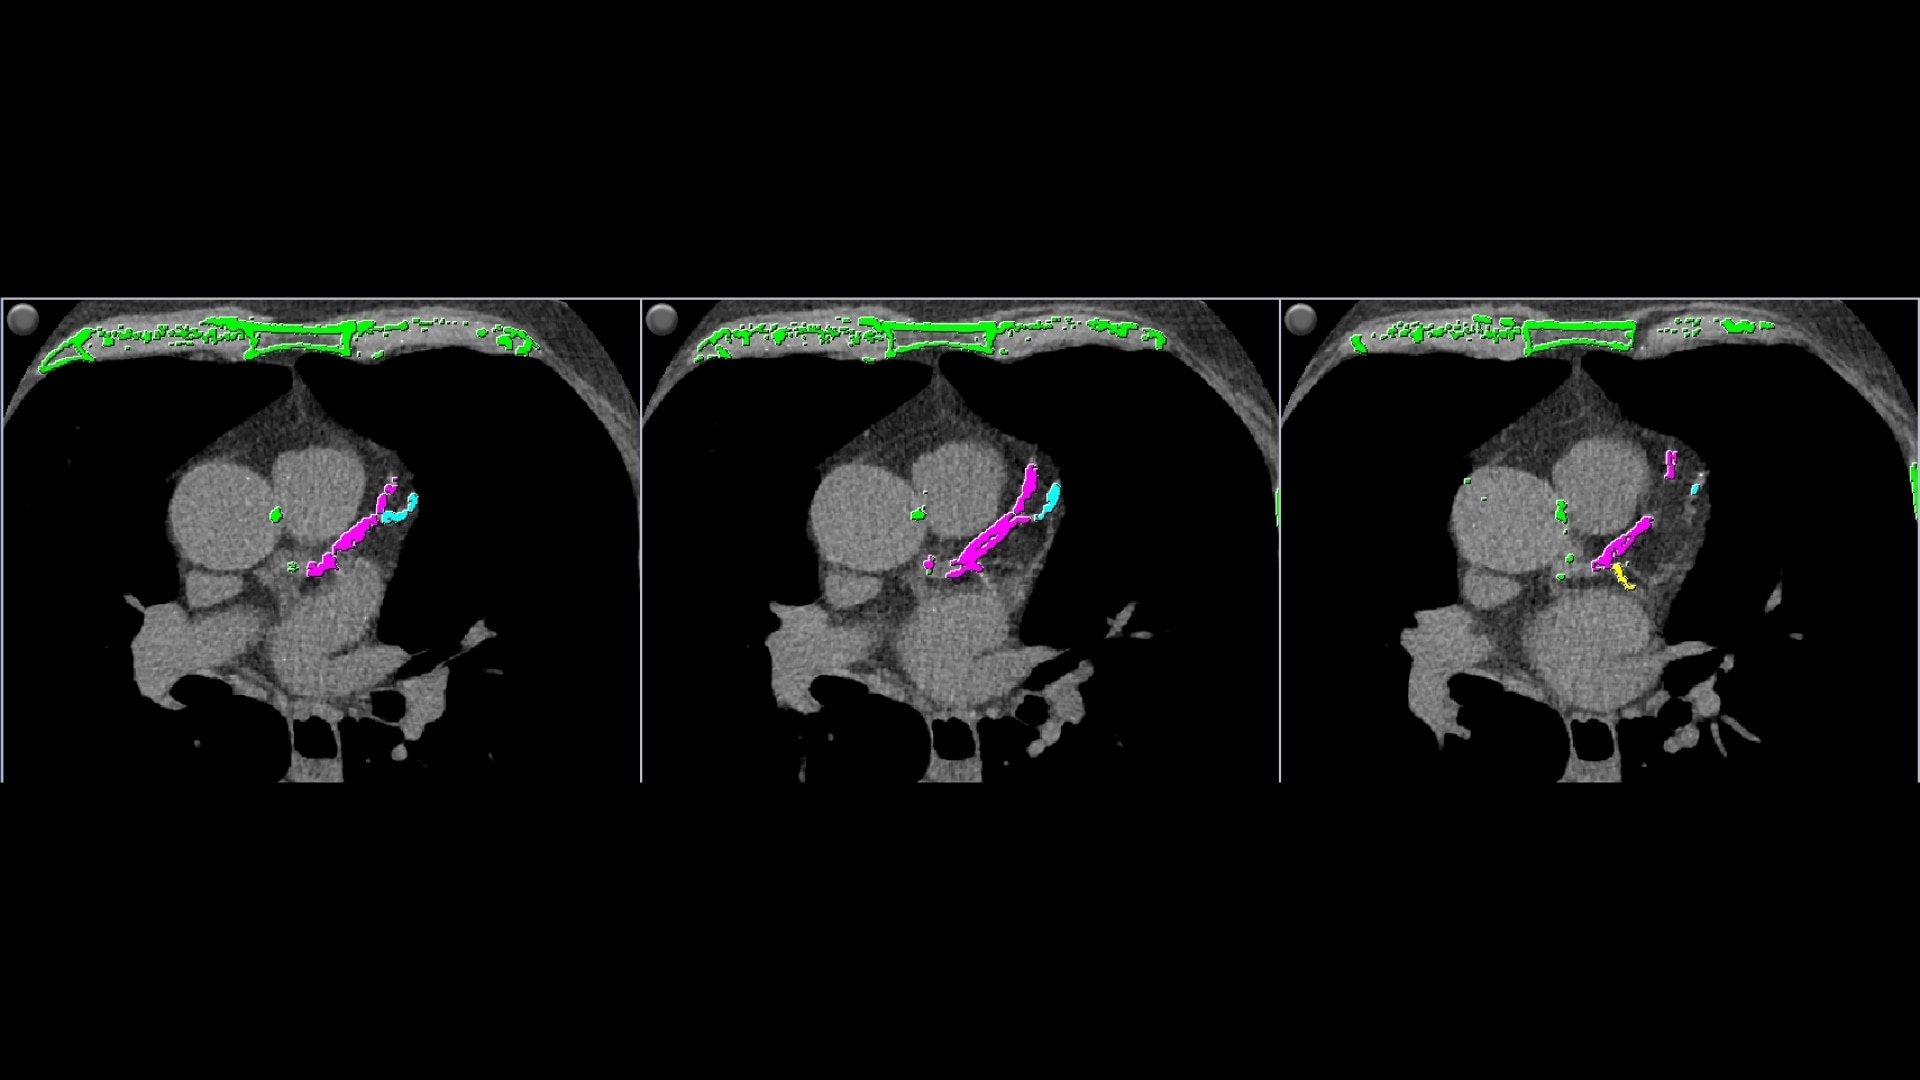

• Automatically detects calcium and highlights it in green

• AJ 130 scoring method uses conventional Agatston/Janowitz technique with a threshold of 130

• HU which is adjusted to the appropriate image slice thickness